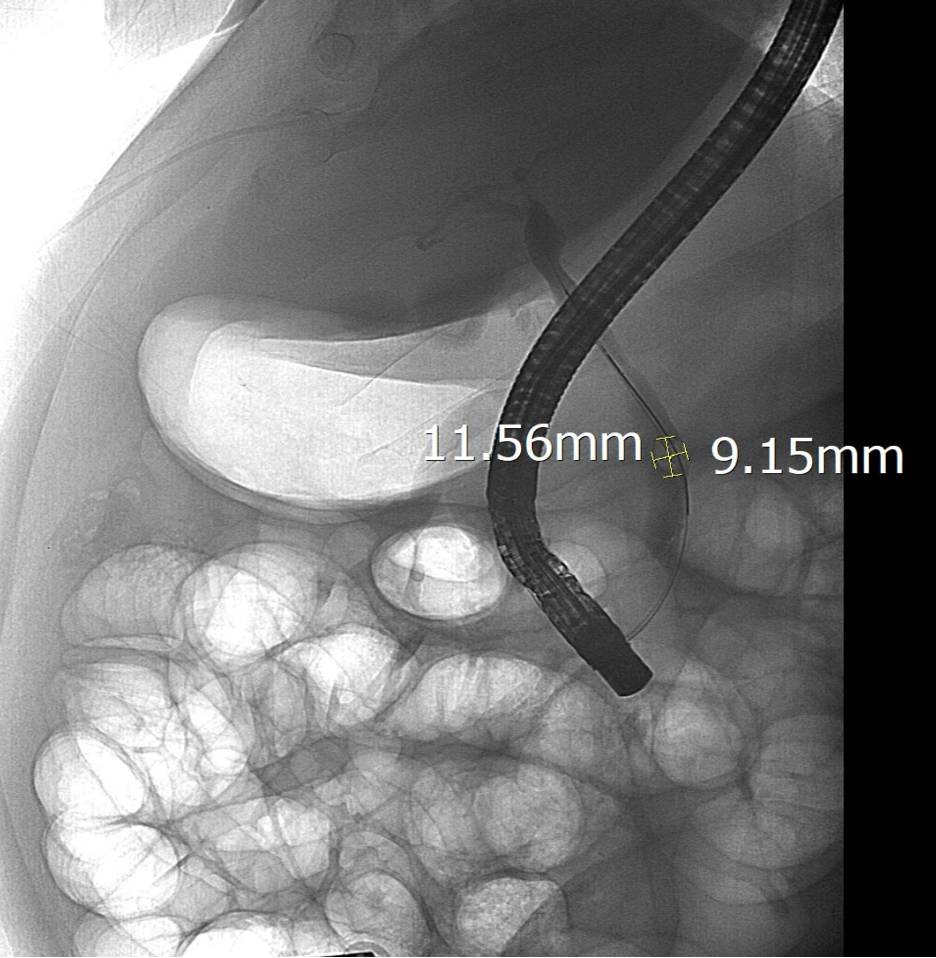

Sau khi hội chẩn, các Bác sĩ Khoa Nội Tiêu hóa đã chỉ định nội soi mật tụy ngược dòng (ERCP) dưới hướng dẫn của hệ thống chụp mạch số hóa xóa nền (DSA). Trong quá trình can thiệp, ê-kíp đã lấy thành công viên sỏi kích thước 11,5 x 9 mm, giải phóng tình trạng sỏi ống mật chủ. Sau thủ thuật, tình trạng vàng da và đau tức của người bệnh cải thiện rõ rệt, chức năng gan mật dần ổn định, thời gian điều trị được rút ngắn.

Ca can thiệp được thực hiện cho bệnh nhân Đ.T.L (66 tuổi, ở tổ 7, phường Hà Giang 1). Bệnh nhân nhập viện trong tình trạng đau hạ sườn, vàng da, men gan tăng cao, định lượng bilirubin máu cao. Qua khám, chẩn đoán bệnh nhân bị tắc mật do sỏi ống mật chủ với viên sỏi kích thước 12 x 8mm, gây ứ trệ dịch mật, tăng men gan và bilirubin máu.